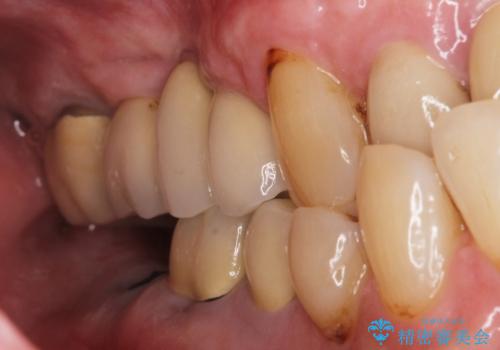

【インプラント】 他院で入れた被せ物が取れた

- 「他院で治療した被せ物が外れた」を主訴に来院された患者様です。診査診断を行い歯の保存が困難だったため抜歯後、インプラントで治療しました。